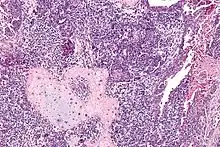

Carcinosarome utérin. HE, x250